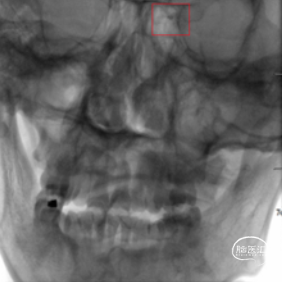

头颈CTA :左侧颈内动脉末端及基底动脉重度狭窄或闭塞。

术前CTA检查。

术前造影,BA近端闭塞。

术前造影,LC7次全闭塞。